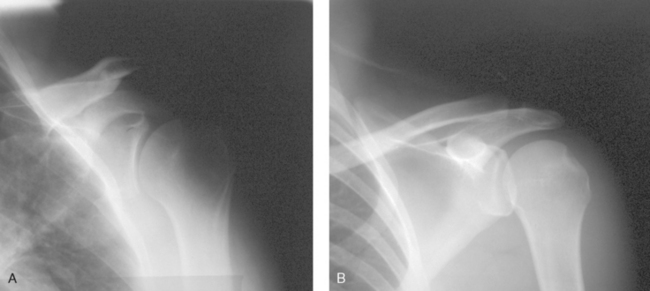

Fig. 2-11 A, AP projection of shoulder without compensating filter. B, Same projection using Boomerang contact filter.